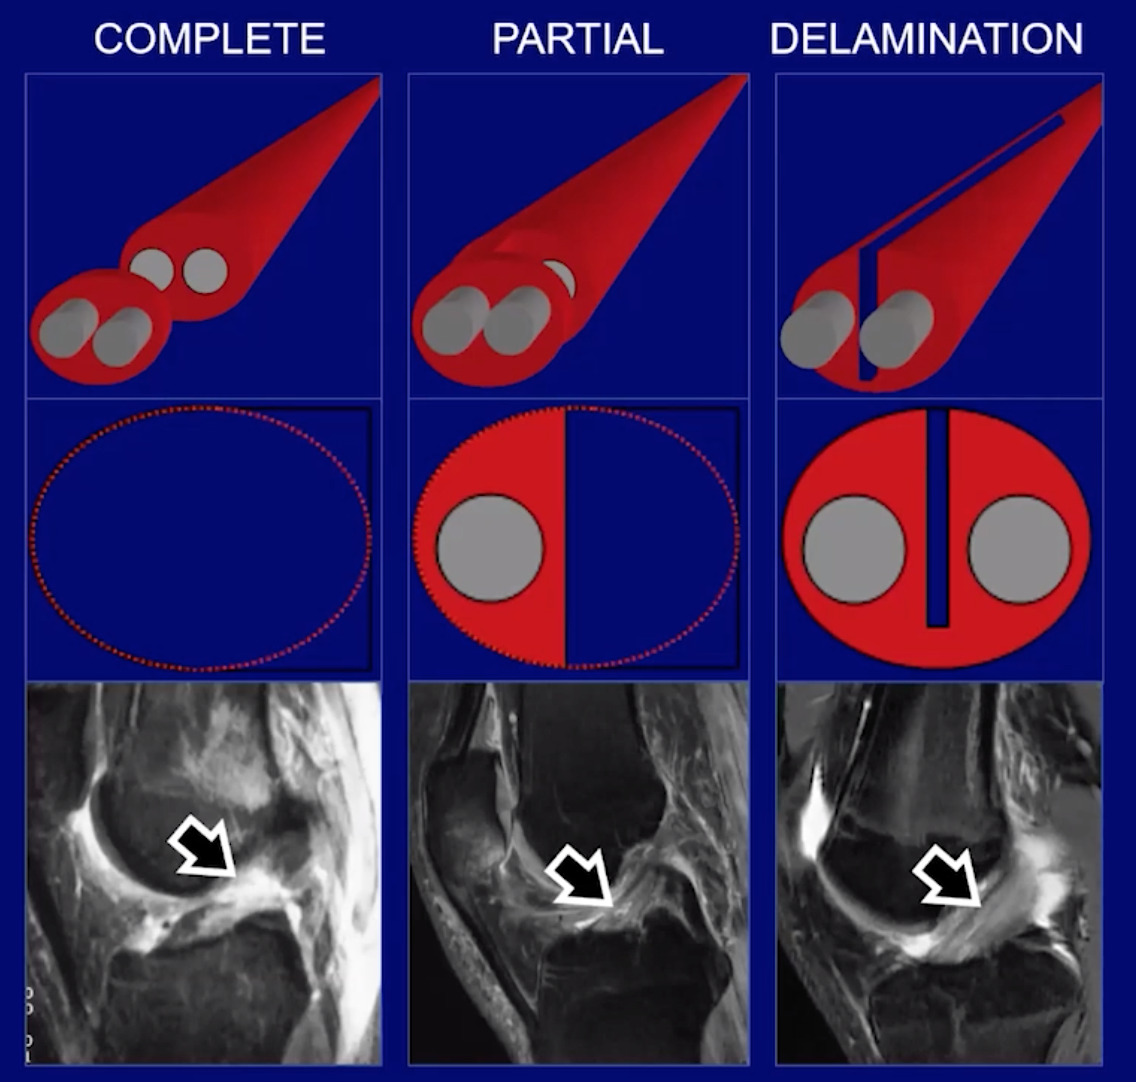

Ligament Injury

• Complete

• Partial

• Delamination